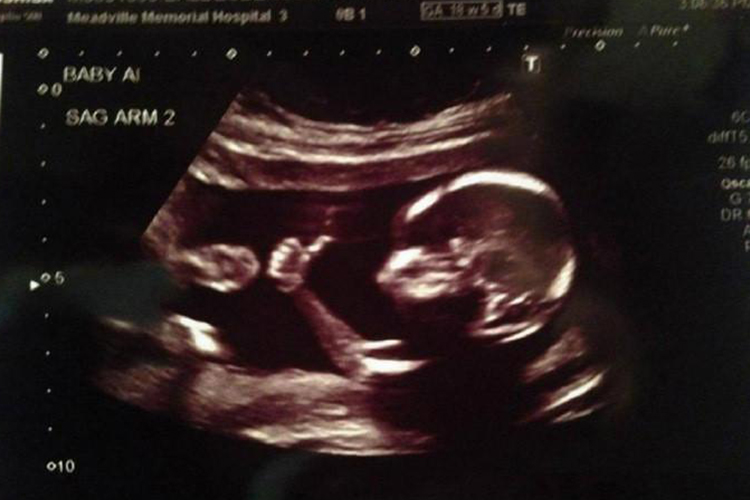

通常大排畸检查的最佳时机为孕20-24周,此阶段胎儿各器官结构已基本形成,且羊水适中,便于超声图像的清晰显示,从而确保检查的准确性。大排畸检查作为孕期重要的产前筛查手段之一,可全面评估胎儿的生长发育情况,排查是否存在结构异常。

- 孕20-24周是进行大排畸检查的理想时间窗口,此时胎儿大小适中,活动空间较大,便于超声医生从不同角度观察胎儿的各个部位,包括头部、脊柱、心脏、四肢及内脏等,以全面评估其发育状况。